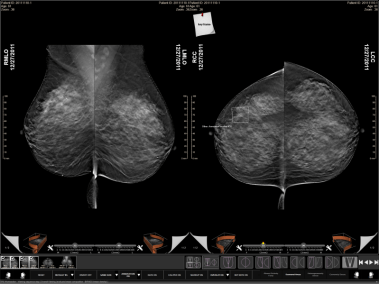

CAD is the term we used for 90s AI as it applied to screening mammography. Mammography being x-rays of breasts, performed to look for breast cancer. The methods used were mostly expert systems using handcrafted rules and support vector machines with hand-crafted features (SIFT/HOG etc).

Example of a CAD interface, with a highlighted area of concern.